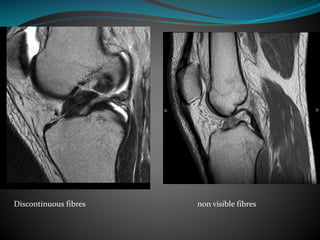

ACL Tear

Acute-

 Replacement of normal striated appearance by cloud

like high signal intensity

 Discontinuity of ligament and fibres don’t go parallel to

intercondylar roof

Chronic-

Nonvisualisation of ligament or

Angulation of ligament because of scarring

Shallow orientation not parallel to intercondylar

roof

Normal Acute tear

Discontinuous fibres non visible fibres

Chronic tear